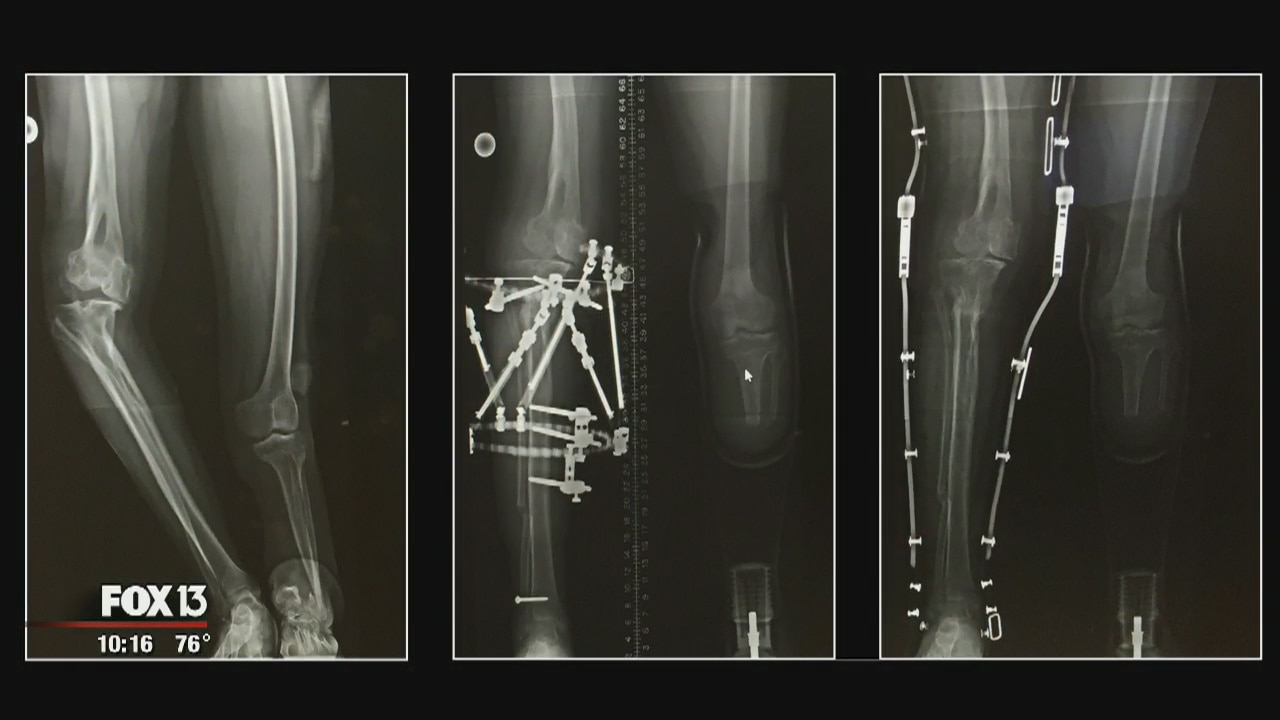

He arrived in Tampa back in April, 2016 as a 17-year-old prisoner to a pair of legs. One had grown crooked, and the other only grew half-way. Now he has a new prosthesis and an even better outlook on life.